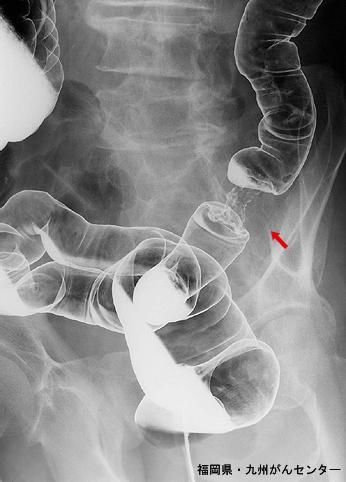

几乎累及全周的典型的2型(局限溃疡型)进展期大肠癌

恶性上皮性肿瘤/腺癌

大肠/降结肠

X线

2型(溃疡局限型)/

40以上

s(a)